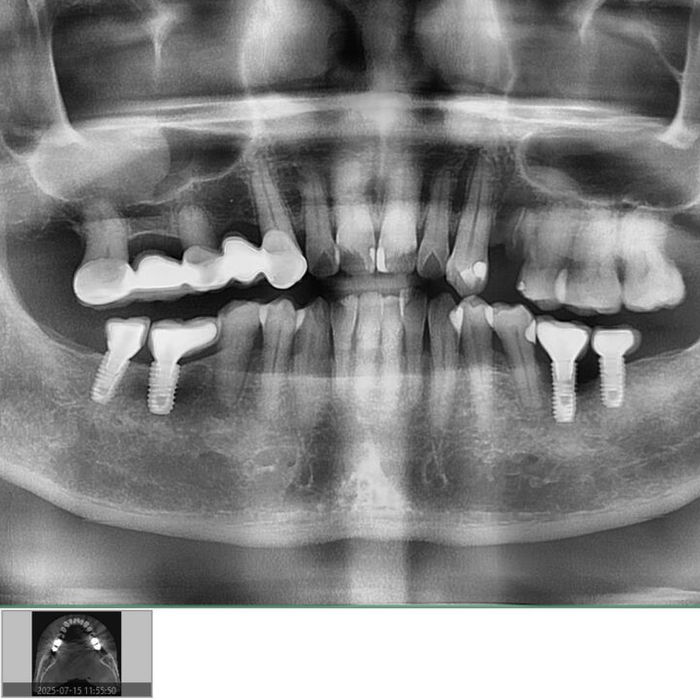

How do you know if I have retained roots?

X-rays or 3D imaging reveal fragments that may not be visible or causing symptoms yet.